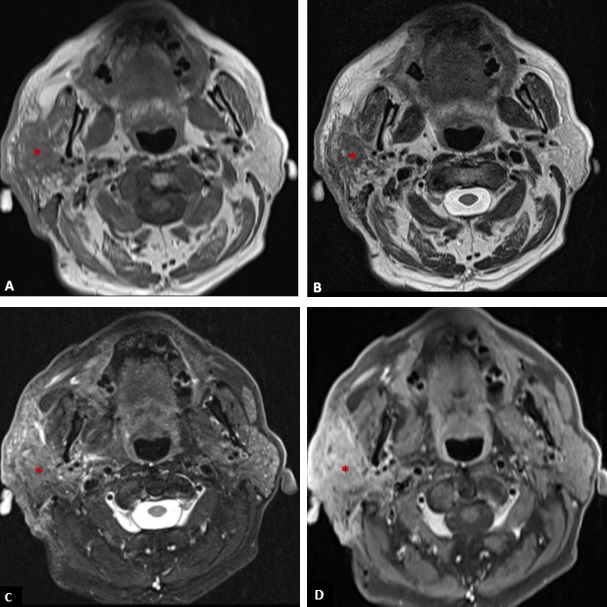

The patient denied a history of recent trauma. There was no evidence of facial paralysis or pain during palpation. A painless fibroelastic lymph node of about 1 cm was apparent at the right cervical level II. Facial/Cervical magnetic resonance imaging (MRI) and cervicothoracic computed tomography (CT) were performed, showing a diffuse infiltrative process of the right parotid gland, mimicking an inflammatory process (Fig. 2 and 3). The lesion showed a low signal on T1 and a heterogeneous signal on T2-weighted images, with heterogeneous post-contrast enhancement.

Figure 3: T1-weighted axial image (A), T2-weighted axial image (B), fat suppressed T2-weighted axial (C), and post-contrast fat suppressed T1-weighted axial image (D) showing an infiltrative mass (*) in the right parotid gland with low signal on T1, heterogeneous signal on T2 (with areas of high and low signal), and heterogeneous enhancement invading the adjacent fat, skin and the right masseter muscle.